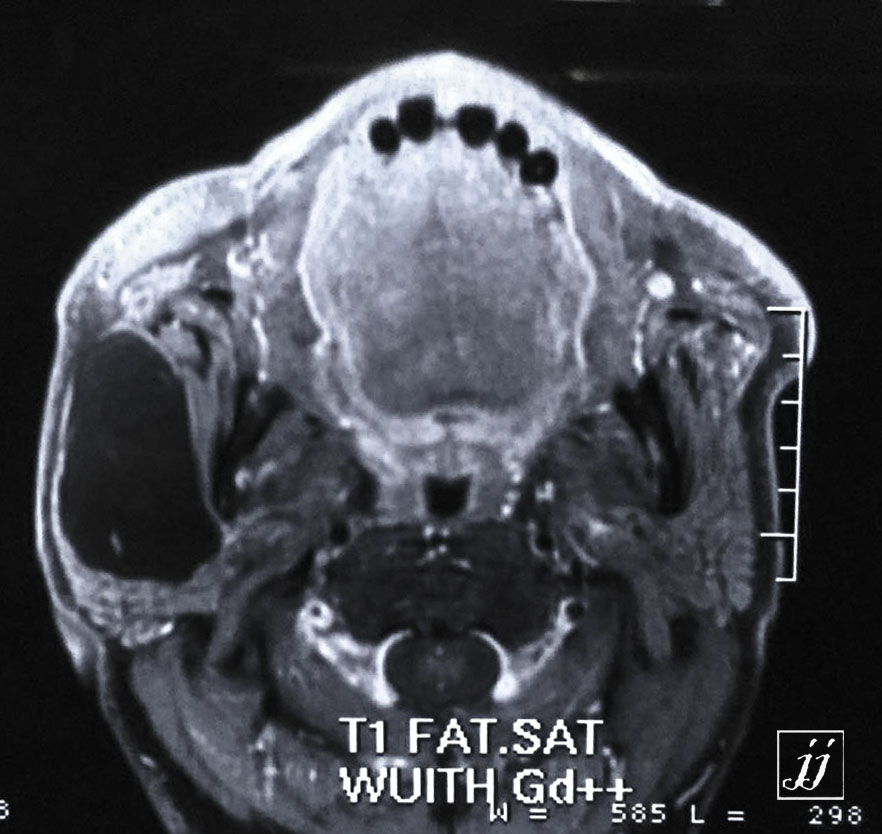

Brain- large masseter muscle cystic lesion (2)